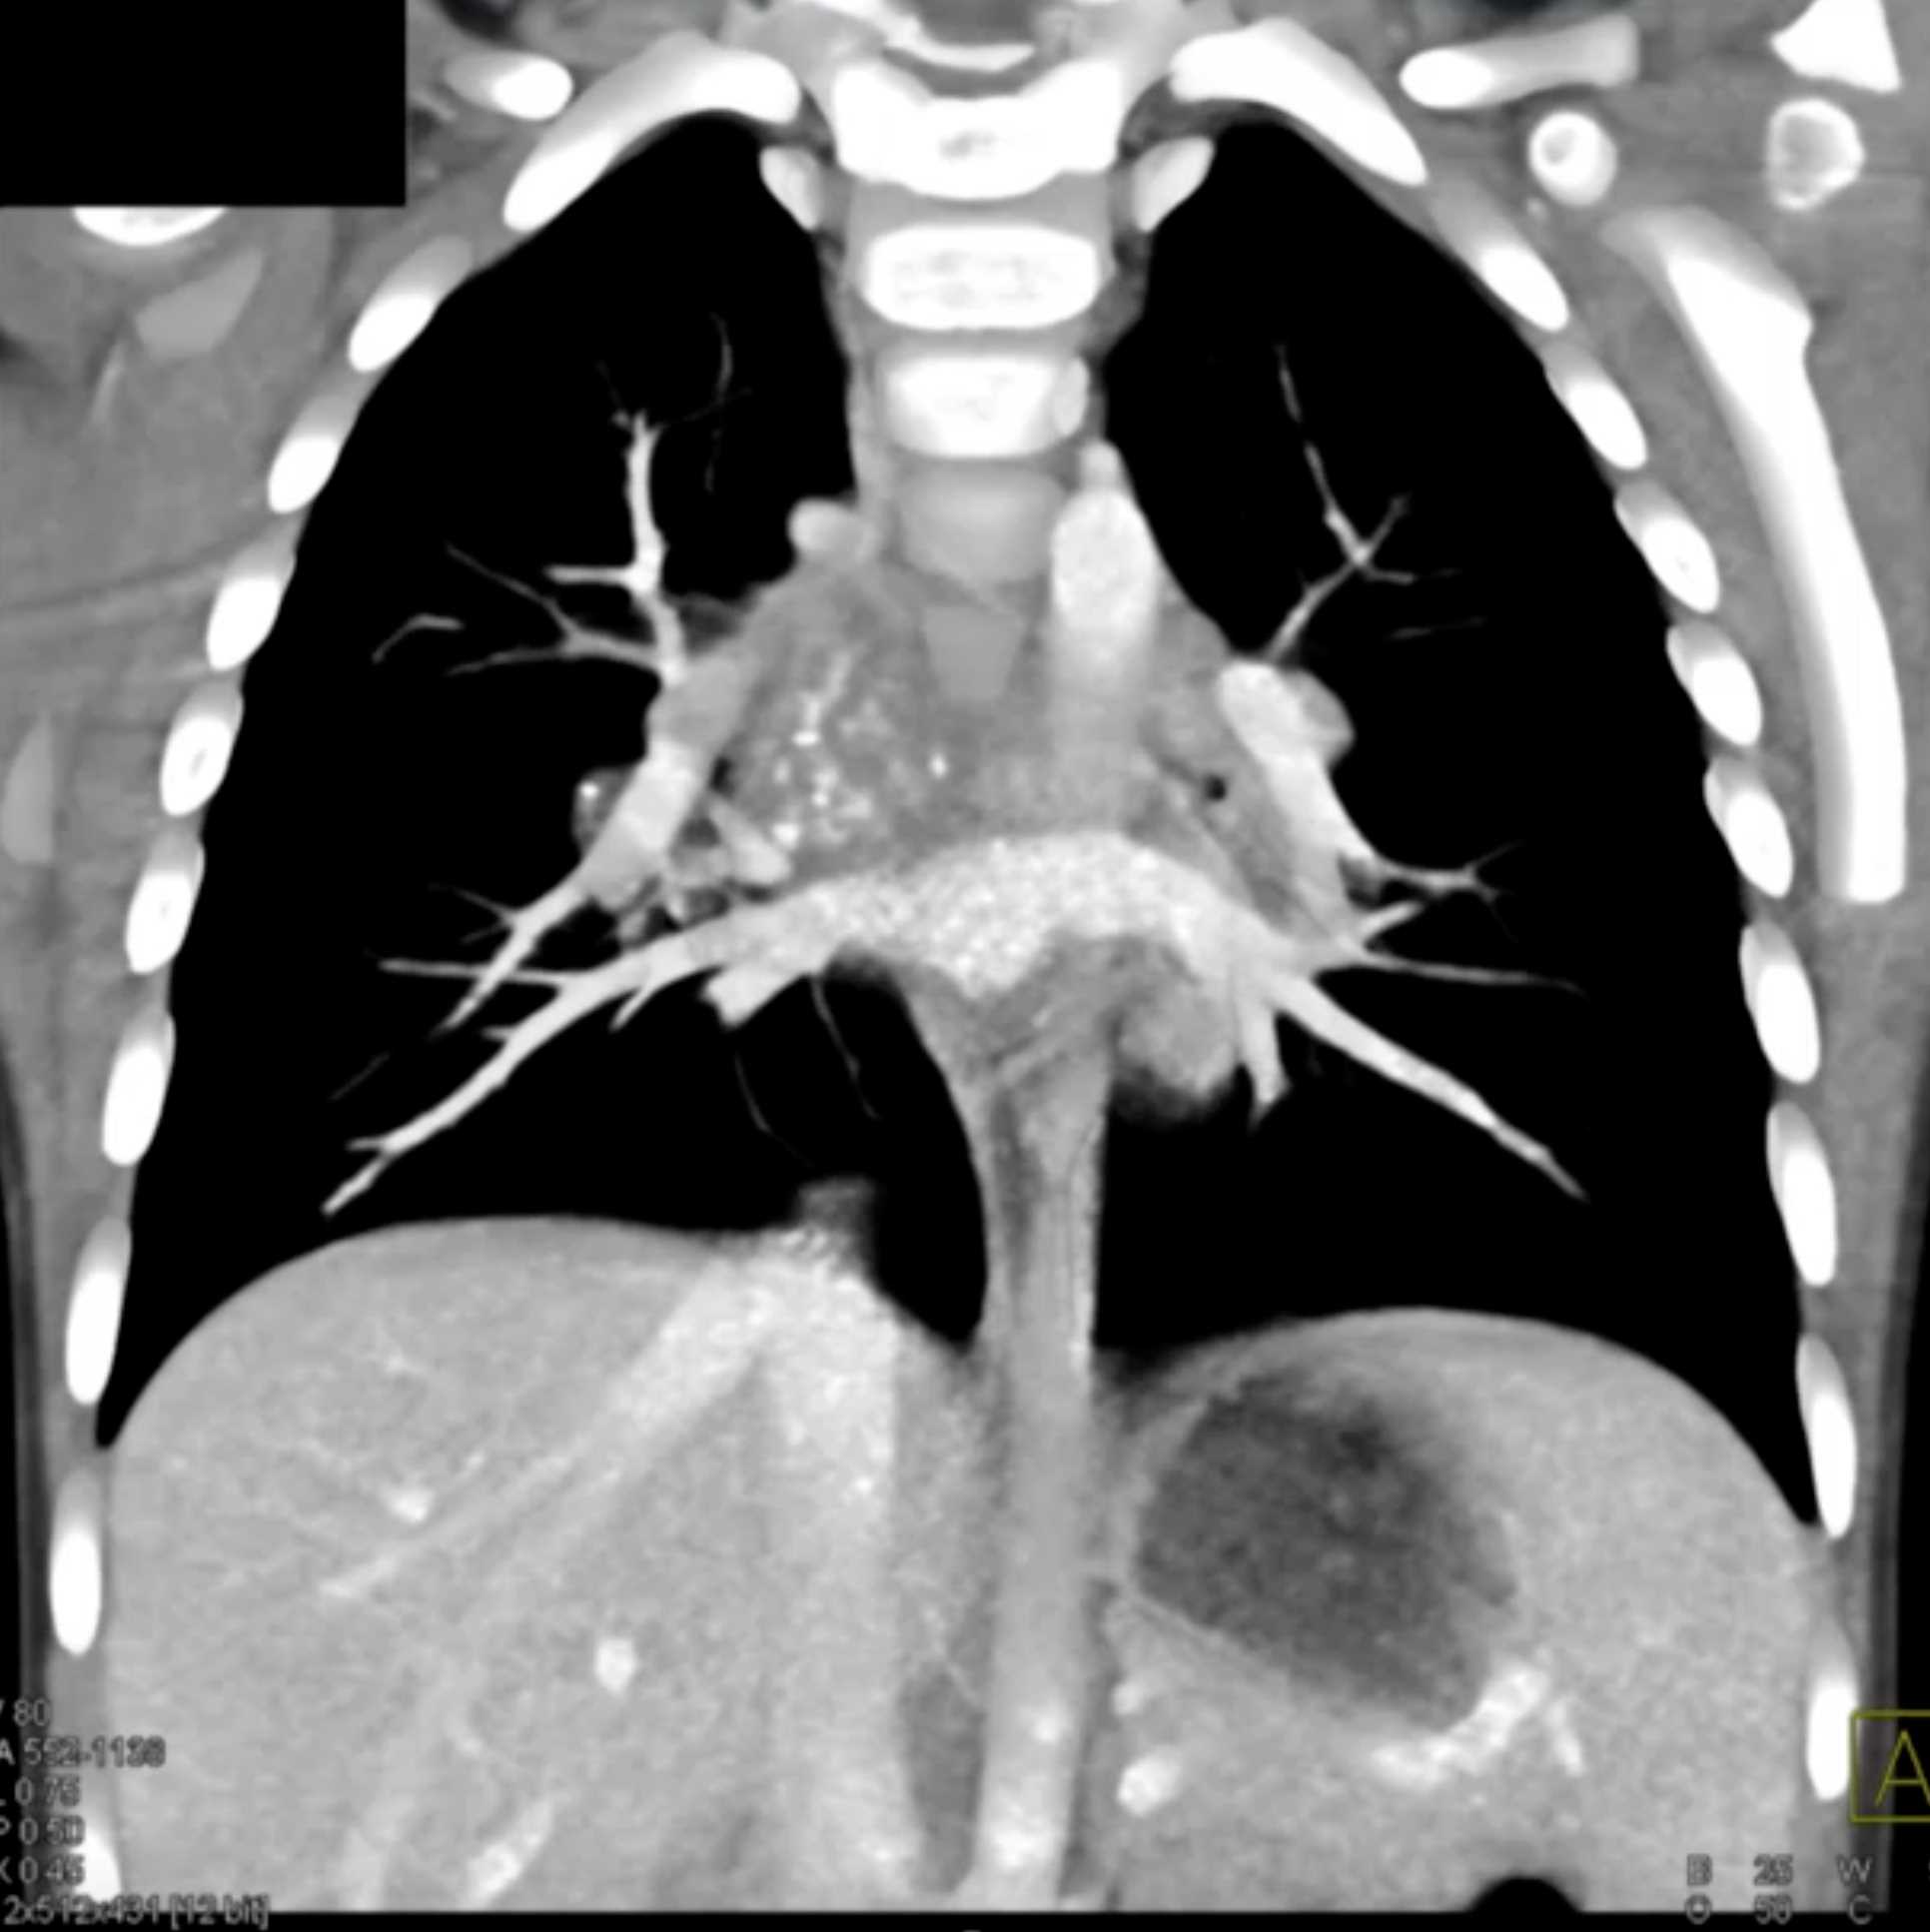

Histoplasmosis and Normal Thymus